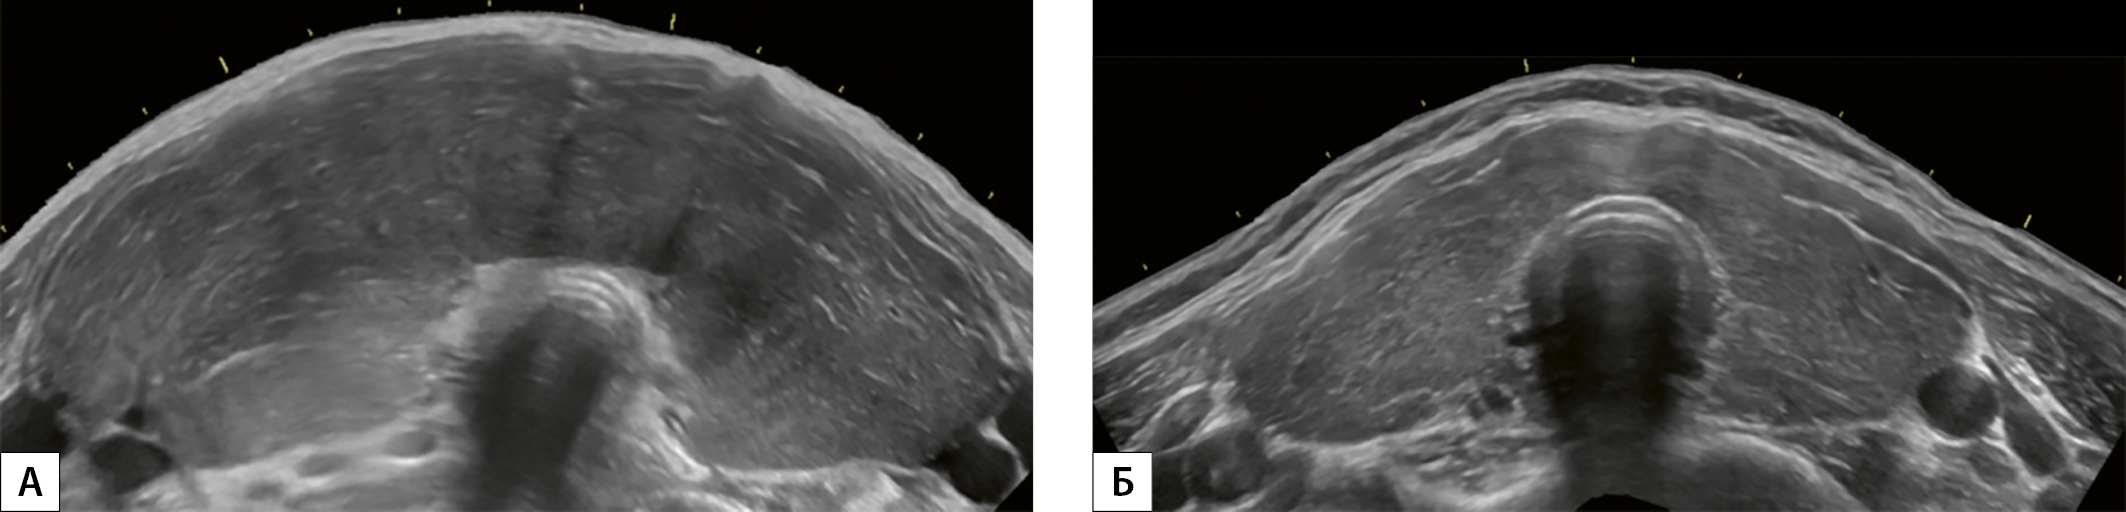

4. Рисунок 4. Эхограммы ЩЖ, выполненные в поперечной плоскости по методике панорамного сканирования на уровне среднего сегмента (перешейка). А — мужчина, 42 года. В левой доле ЩЖ выявлено одиночное объемное образование размерами 26х20х47 мм. Дополнительно в правой доле выявлено два объемных образования максимальным размером 7 и 13 мм. Признак «эхогенность железы» не изменен. Размеры увеличены. Б — мужчина, 55 лет. В правой доле ЩЖ выявлено одиночное объемное образование размерами 24х18х32 мм. Эхогенность железы диффузно понижена. Размеры увеличены.